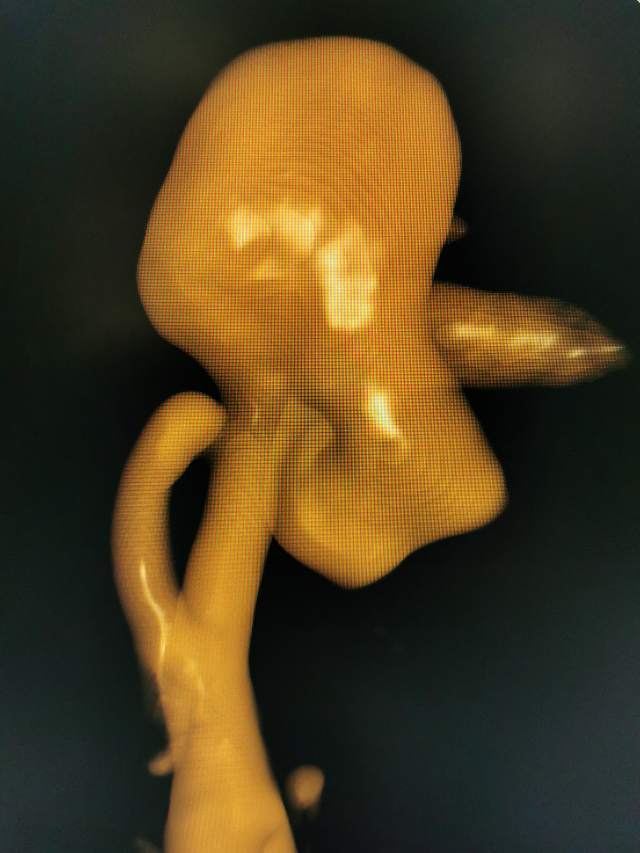

福建中年女性,近期在外查出“颅内动脉瘤”,经推荐转来我院诊治。患者的颈内动脉通路迂曲,动脉瘤也位置奇特,解剖复杂,动脉瘤远近段的血管弯弯绕绕,重重叠叠,眼花缭乱,难以兼顾找到最佳位置。最终克服困难,将“基底型”动脉瘤改变为“侧壁型”动脉瘤,顺利给予治疗……